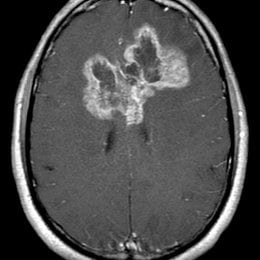

PREGUNTA 1 de 10

¿Cuál es el diagnóstico más probable de la siguiente imagen?

A)

quiste aracnoideo

B)

Quiste de la bolsa de Rathke

C)

craneofaringioma

D)

Silla turca vacía

E)

macroadenoma hipofisario